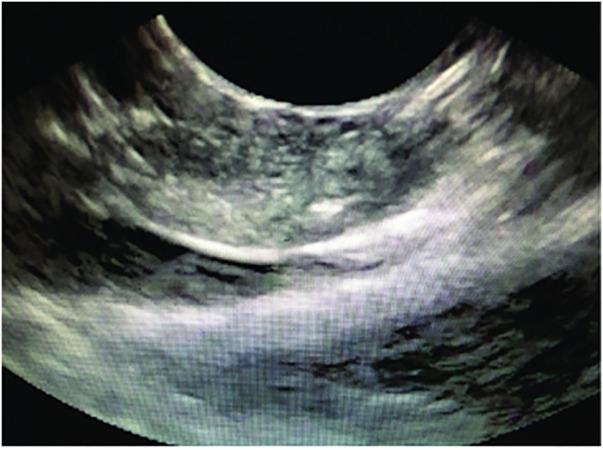

Pancreatic cystic lesions can be benign, premalignant or malignant. The recent increase in detection and tremendous clinical variability of pancreatic cysts has presented a significant therapeutic challenge to physicians. Mucinous cystic neoplasms are of particular interest given their known malignant potential. This review article provides a brief but comprehensive review of premalignant pancreatic cystic lesions with advanced endoscopic ultrasound (EUS) management approaches. A comprehensive literature search was performed using PubMed, Cochrane, OVID and EMBASE databases. Preneoplastic pancreatic cystic lesions include mucinous cystadenoma and intraductal papillary mucinous neoplasm. The 2012 International Sendai Guidelines guide physicians in their management of pancreatic cystic lesions. Some of the advanced EUS management techniques include ethanol ablation, chemotherapeutic (paclitaxel) ablation, radiofrequency ablation and cryotherapy. In future, EUS-guided injections of drug-eluting beads and neodymium:yttrium aluminum agent laser ablation is predicted to be an integral part of EUS-guided management techniques. In summary, International Sendai Consensus Guidelines should be used to make a decision regarding management of pancreatic cystic lesions. Advanced EUS techniques are proving extremely beneficial in management, especially in those patients who are at high surgical risk.